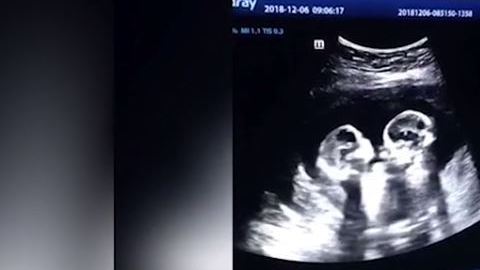

Las gemelas parecieran darse unos cuantos golpes.

En el ultrasonido se puede ver el momento exacto en el que estas gemelas pareciera que estuvieran peleando entre ellas, pues hacen movimientos como si se patearan o golpearan mutuamente con sus manos.